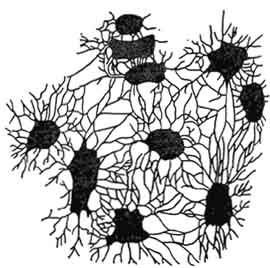

Структура грубоволокнистой костной ткани: наглядные примеры